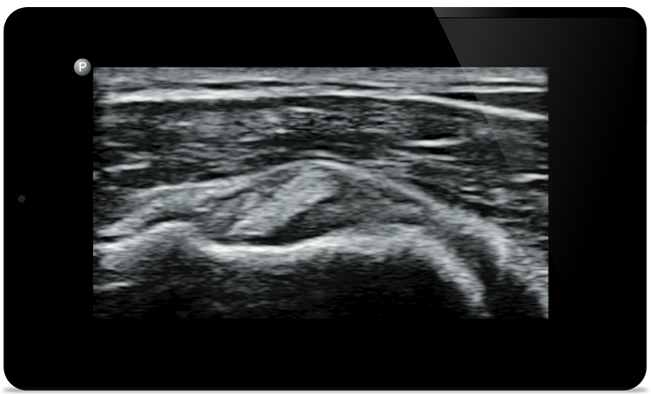

Lumify vă ajută să vedeţi detaliile fine ale muşchilor, articulaţiilor, ligamentelor, tendoanelor şi cartilagiilor pentru a pune un diagnostic mai precis al leziunilor.

Lumify vă poate ajuta să evaluaţi pacienţii din cap până în picioare, fie că este vorba de fasceită plantară, tendinită sau bursită la nivelul tendonului rotulian, sau chiar de instabilitatea umărului la nivelul centurii scapulare.